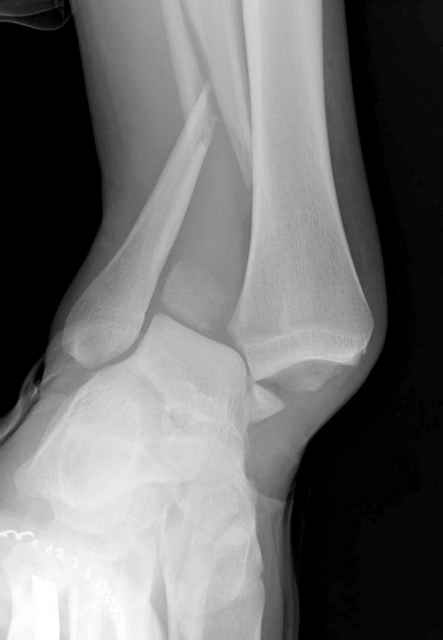

Конечно, компьютерный томограф более информативный метод, но с помощью недорогого обычного стандартного в нейтральном положении стопы: прямого, бокового и косой (ankle mortise) ренгенологического метода можно получить полную информацию о повреждении голеностопного сустава, а сравнительный снимок с другой стороны подтвердить наличие повреждения.

При реконструкции голеностопа, о важности восстановления длины малоберцовой для профилактики пост травматического артроза разбирали в предыдущих дискуссиях. Нарушенную биомеханику голеностопа без восстановления длины малоберцовой, не восстановить только швом медиальной связки.

Расширенная медиальная щель более чем на 4 мм и укорочение малоберцовой более чем 2 мм, а перелом заднего края большеберцовой смещения более 2мм с вовлечением 30% поверхности сустава, считается отходом от нормы голеностопного сустава, и подлежит к оперативному вмещательству.